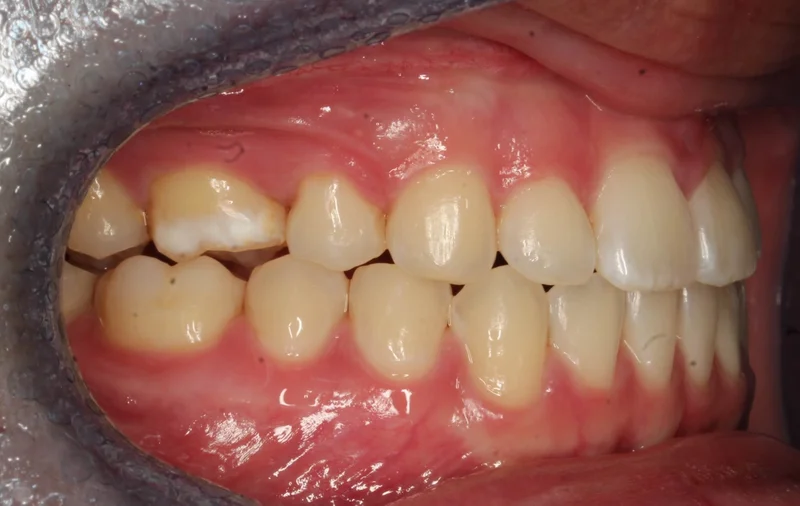

Case #90850 | 18 - 29 | Female

This young woman in Las Vegas came to us with a severe class III malocclusion (underbite) and the only option to correct her bite was with extractions on the upper arch and orthognathic surgery with an oral surgeon. She needed to have two teeth extracted first on the upper arch as part of the presurgical orthodontics to correct the severe proclination of the upper incisors. We first decompensated for this proclination by uprighting the upper incisors and closing the extraction space, which actually makes the overjet worse prior to surgery. She then had a double jaw surgery, including a Le Fort maxillary advancement as well as a mandibular setback. After about 6 weeks of post-surgical healing, she resumed orthodontic treatment to finish up. Her total treatment time was 27 months.

Right Buccal - Before Treatment

Before